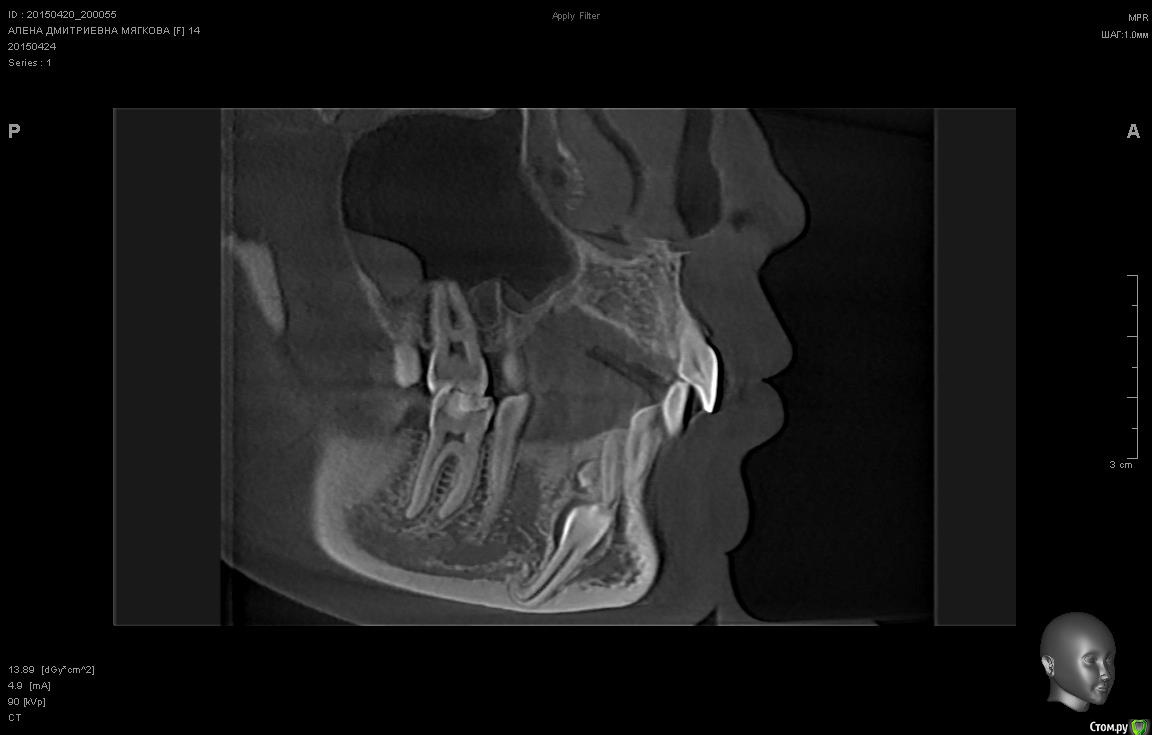

sgeorge Опубликовано 24 апреля, 2015 Автор Поделиться Опубликовано 24 апреля, 2015 Вот некоторые срезы. Вопрос в том, стоит ли браться за ортодонтию. Ортодонта сегодня нет, спросить не могу. Ссылка на комментарий

sgeorge Опубликовано 24 апреля, 2015 Автор Поделиться Опубликовано 24 апреля, 2015 Как-то криво прикрепились, сорри.Думаю, что с таким крючком на апексе ортодонтия отпадет? Тогда стоит ли удалять в настоящий момент или дождаться завершения роста челюсти? Ссылка на комментарий

krokomot Опубликовано 24 апреля, 2015 Поделиться Опубликовано 24 апреля, 2015 Клык то молочный во рту, без ортодонтии все равно не обойтись так что можно попробовать зуб вертикально почти стоит, только кортикалку желательно бы удалить по ходу выдвижения (постепенно). На стрелке думаю одонтома при раскрытии убрать. Ссылка на комментарий

sgeorge Опубликовано 26 апреля, 2015 Автор Поделиться Опубликовано 26 апреля, 2015 Жалобы на самопроизвольные мигрирующие боли верхней и нижней челюсти справа в течение последней недели. Прикус ортогнатический, на месте 43 молочный 83, подвижность 1 степени. Множественный кариес, гигиена полости рта неудовлетворительная. Ссылка на комментарий

sgeorge Опубликовано 29 апреля, 2015 Автор Поделиться Опубликовано 29 апреля, 2015 Значимость клыка вполне ясна. Сильно смущает загнутая верхушка корня, позволит ли это переместить зуб на столь немаленькое количество милиметров Ссылка на комментарий